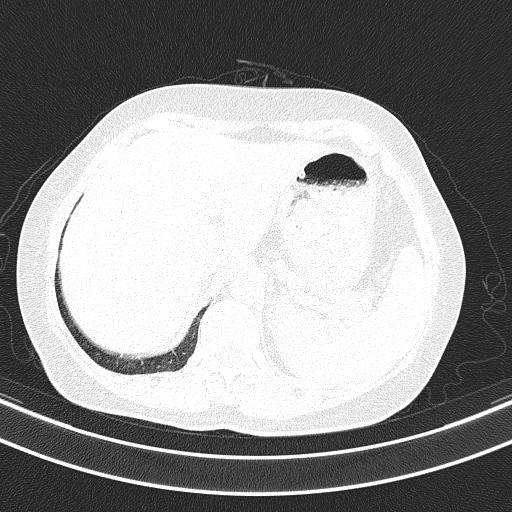

CT50872:右下肺这个是大泡还是含气囊肿

右下肺这个是大泡还是含气囊肿

左支扩、右囊肿

支气管囊肿

壁比较厚,壁内见血管影,囊肿可能性大

肺囊肿

考虑两肺支气管囊肿

肺大泡